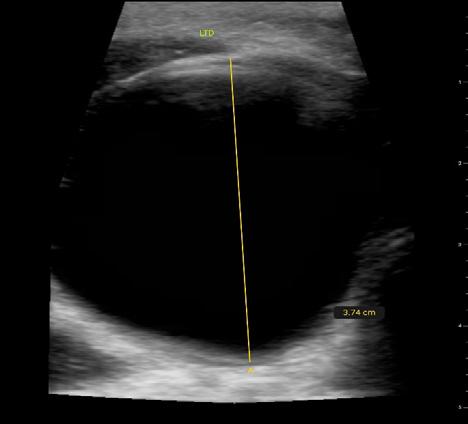

Issuu converts static files into: digital portfolios, online yearbooks, online catalogs, digital photo albums and more. Sign up and create your flipbook.